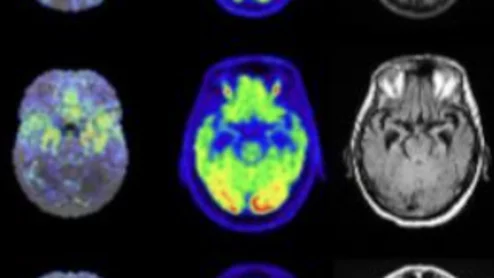

HeartFlow Plaque Analysis Example

The use of advanced AI software to assess CCTA images continues to gain more momentum.